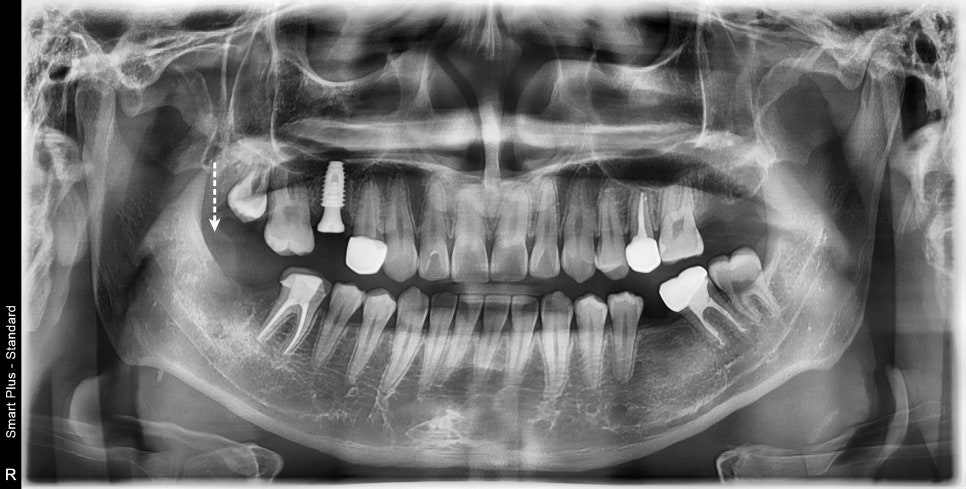

길을 내어주고 3달이 지났습니다.

그동안 안 좋은 치아들을 치료하고 있었습니다.

엑스레이 상으로도 치아는 맹출 되고 있는 것을 볼 수 있습니다.

뿌리도 조금 성장한 것으로 보입니다.

해당 치아는 강한 고정력을 가하지 않고

치근이 성장하며 맹출 되기를 지켜봐야 할 것입니다.